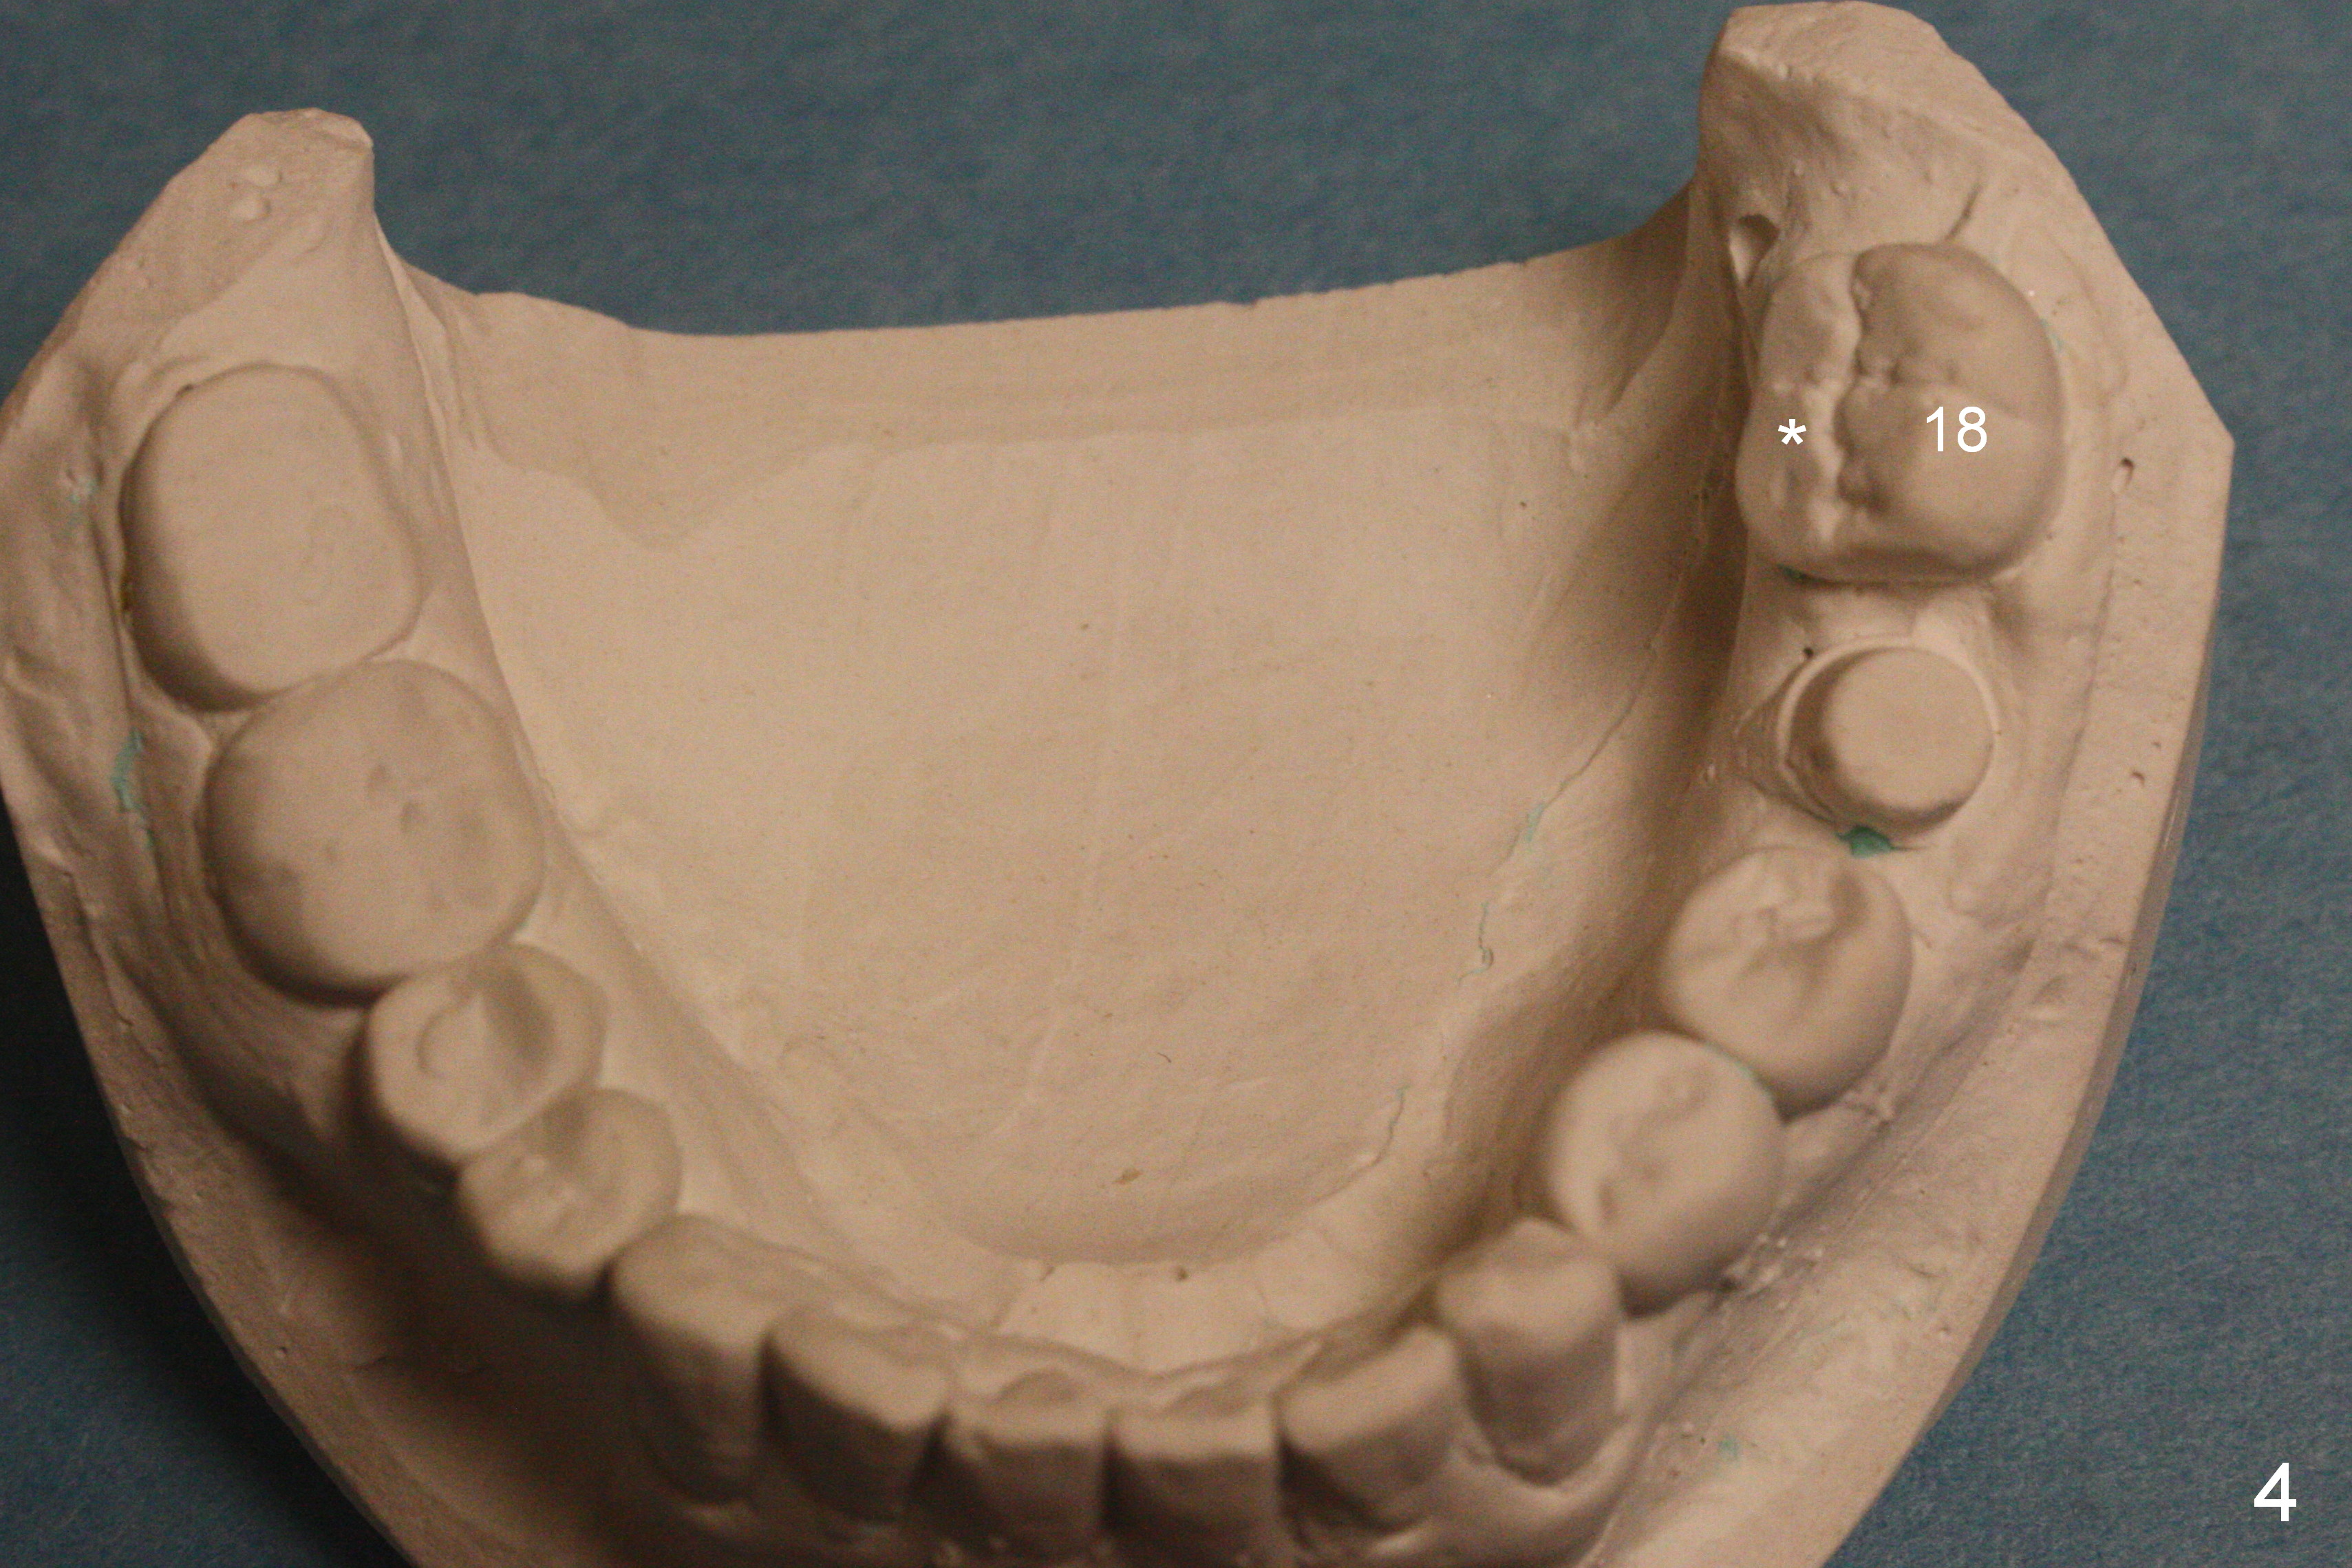

A 40-year-old man had automobile-related mandibular fracture and surgical reduction several years ago.  Since then there has been cross bite in the left molar region (Fig.1-2) with abnormal wear facets in the occlusal surface of the teeth #14, 15 and 18 (Fig.3,4 *).  At the time of implant placement at #19, the patient reports tooth sensitivity at #15 and wonders whether increase in the occlusal surface of the future crown at #19 can alleviate the tooth sensitivity or not.  In fact the tooth #14 and 19 were in cross bite when the sites of #20 and 21 were processed for implant crowns (Fig.1).  The cross bite of the left molar area appears to be so severe that surgical segmental osteotomy or orthodontic treatment is required (Fig.5-7).